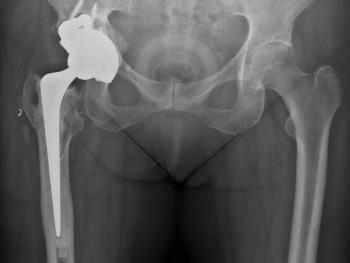

Clinical cases: variations of Exeter stem size and offset copes with almost all abnormal anatomies.

Figure 9 & Figure 10: DDH case – small socket – 40/22mm required. Leg length restored. Modularity of head sizes and offsets allows accurate restoration of leg length and offset.